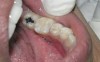

Figure 5  Clinical applications of RBCs for posterior restorations: occlusal caries restored with silorane-based RBC

Figure 5

Figure 6  Clinical applications of RBCs for posterior restorations: occlusal caries restored with silorane-based RBC

Figure 6